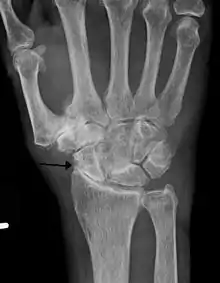

X-rays

Radiographs can confirm the diagnosis of wrist osteoarthritis. The earliest sign is narrowing of the joint space between the radius and the scaphoid and an osteophyte off the tip of the radial styloid. [9]

SLAC

Because SLAC results from scapholunate ligament rupture, there is a larger space between the two bones, also known as the Terry Thomas sign.[10] Scaphoid instability due to the ligament rupture can be stactic or dynamic.[11] When the X-ray is diagnostic and there is a convincing Terry Thomas sign it is a static scaphoid instability. When the scaphoid is made unstable by either the patient or by manipulation by the examining physician it is a dynamic instability.[11]